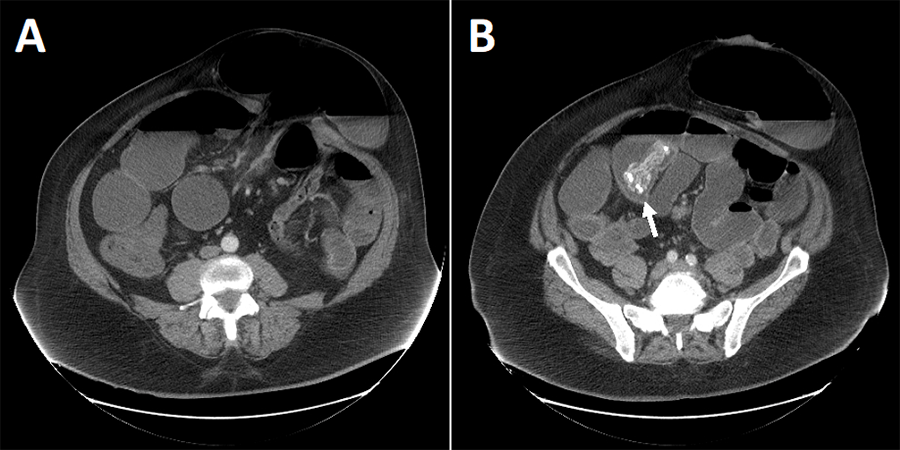

Computed tomography (CT) imagining demonstrated dilated bowel up to 8 cm in diameter with air-fluid levels proximal to and distal to the parastomal hernia consistent with an obstructive process (Figure 1A). Additionally, there was noted to be an intraluminal density of unclear significance within the small bowel, presumed to be fecalized small bowel contents that did not appear to be a source of obstruction (Figure 1B). Compared to two prior annual cancer follow-up CT scans performed one and two years before this study, the size of the parastomal hernia was similar. However, the small bowel proximal and distal to the hernia were notably more dilated in the study shown here. Additionally, prior CT scans did not demonstrate any intraluminal density and showed the mesh at the peritoneal wall with parastomal hernia recurrence.

Figure 1. Computed Tomography (CT) of Abdomen and Pelvis. Published With Permission

Contrast demonstrates A) parastomal hernia sac and loops of dilated bowel and B) intraluminal density within small bowel of unclear significance.